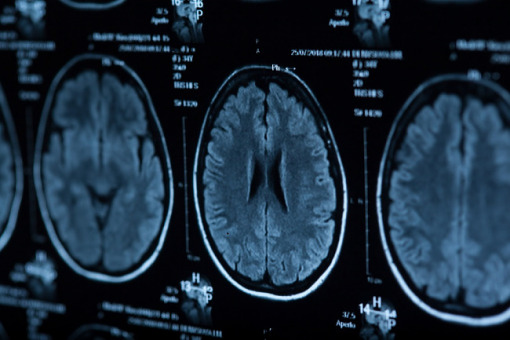

18 pacjentów uczestniczących w badaniu było w wieku 18–75 lat i od 6 miesięcy do 5 lat nie doszło u nich do niedokrwiennego udaru podkorowego środkowego mózgu. Mieli zmodyfikowany wynik w skali Rankina wynoszący 3-4 i stabilny deficyt motoryczny, a także przeszli rehabilitację. Wykluczono pacjentów ze zmianą po udarze < 1 cm3 lub > 100 cm3 w badaniu MRI.